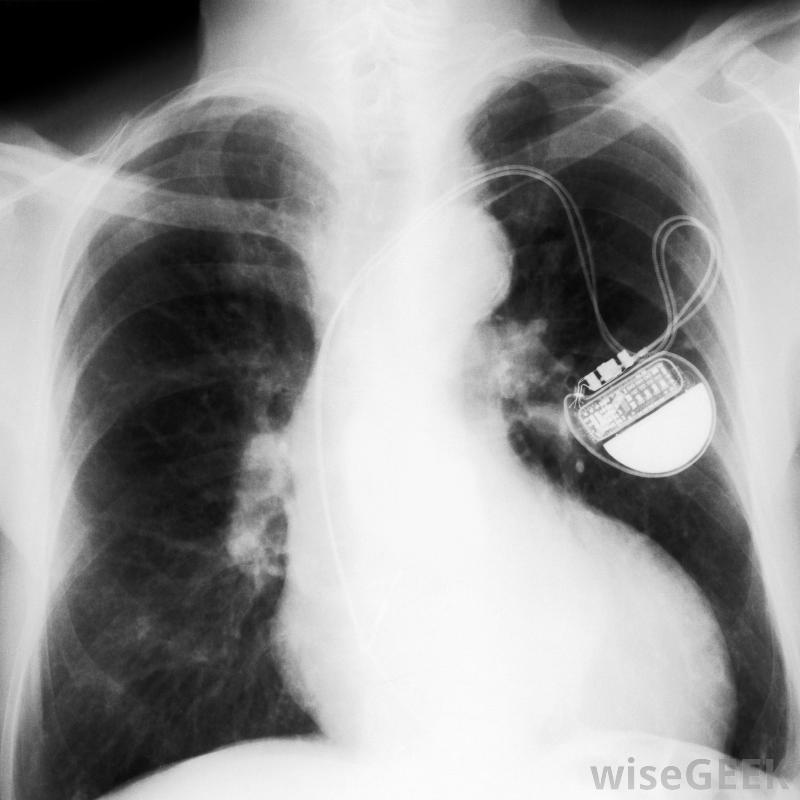

放置過程中,起搏器導線插入胸部左上方的靜脈,與放置發生器的區域相同。醫生通常使用熒光鏡,這是一種X光片,當電線穿過靜脈并進入心臟的適當位置時,可以觀察這些電線。這通常被認為是一個小手術,而且病人通常不需要全身麻醉。手術通常在診所或醫生辦公室進行。

起搏器導線,也叫導線,是一根細線,一端與設備的發電機相連,另一端與心臟相連。每個起搏器可能有兩條或兩條以上的導線連接到右心房和右心室,有時還連接到左心室。導線的一端有一個電極,電極與心臟相連,以獲取心臟的自然電脈沖...

起搏器導線,也叫導線,是一根細線,一端與設備的發電機相連,另一端與心臟相連。每個起搏器可能有兩條或兩條以上的導線連接到右心房和右心室,有時還連接到左心室。導線的一端有一個電極,電極與心臟相連,以獲取心臟的自然電脈沖并將這些信息發送回發生器。